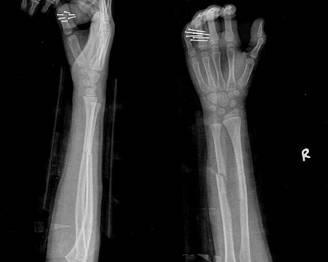

摘要:最新尺橈骨融合方法展現(xiàn)骨頭間的奇妙和諧與友情力量。通過先進(jìn)的醫(yī)療技術(shù),尺骨和橈骨之間的融合得到顯著改善。這種方法不僅提高了治療效果,還展現(xiàn)了人體骨骼之間的和諧關(guān)系。憑借友情和信念的力量,醫(yī)學(xué)界不斷突破,為患者帶來福音。

在醫(yī)生的介紹下,他們了解到了一種最新的尺橈骨融合治療方法——通過微創(chuàng)手術(shù)進(jìn)行骨骼融合的新技術(shù),這種方法不僅減少了手術(shù)風(fēng)險(xiǎn),還能更快地恢復(fù)活動能力,雖然小明感到害怕,但他的朋友們一直陪伴在他身邊,給予他勇氣和力量。